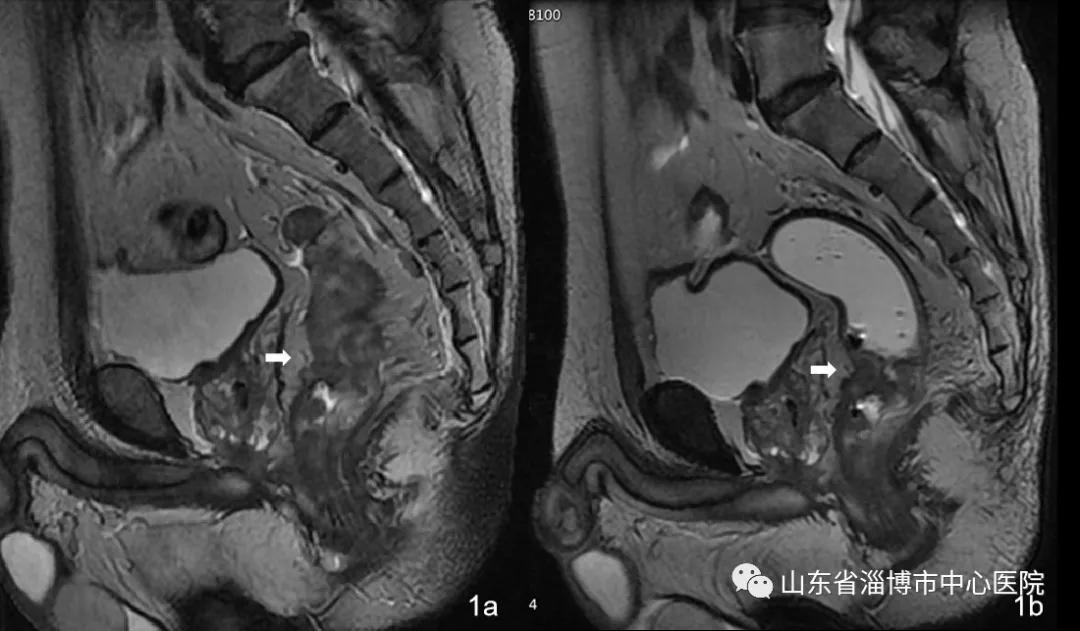

图1a及1b为同一患者耦合剂灌肠前和灌肠后检查的图像,灌肠前病变的位置及累及范围均不易确定,灌肠后检查可清晰显示病变的位置及累及范围。